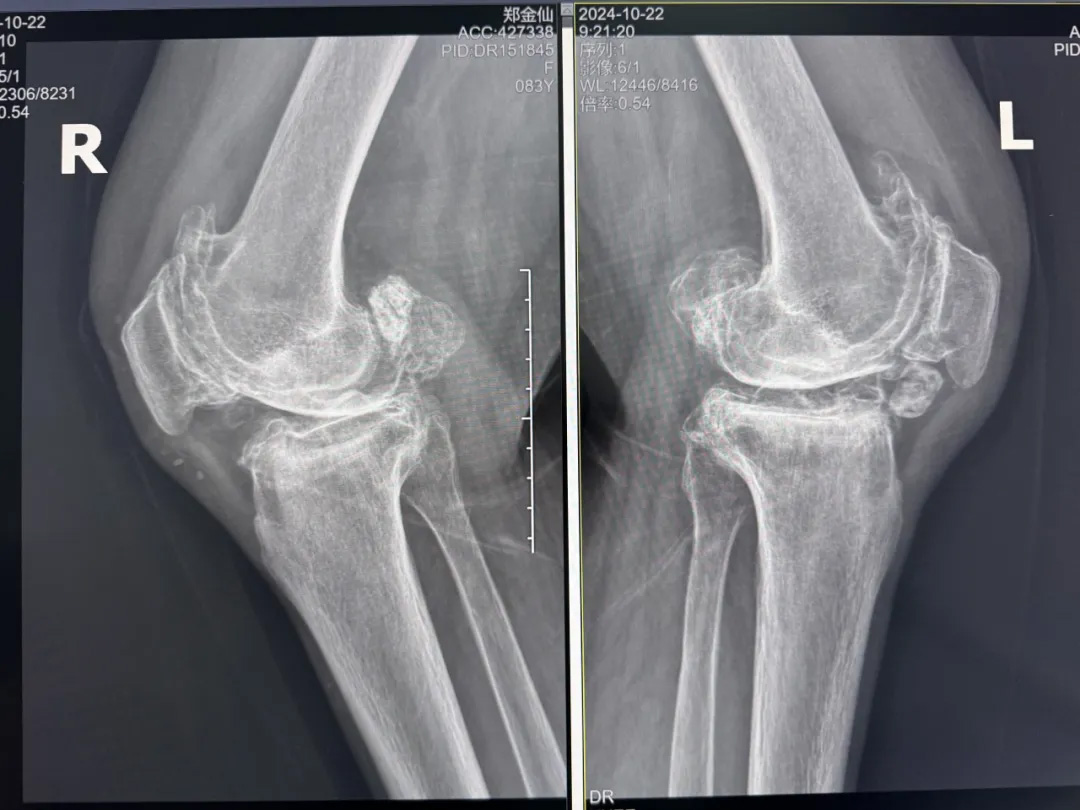

年輕時(shí)愛到處走走的鄭阿婆,晚年卻被雙膝劇痛困在輪椅上長(zhǎng)達(dá)二十年。經(jīng)羅副院長(zhǎng)診斷,她的膝關(guān)節(jié)軟骨幾乎磨光,關(guān)節(jié)嚴(yán)重畸形,呈"羅圈腿",走幾步便疼痛鉆心,連如廁都需家人抱扶。“我這輩子啊,估計(jì)再也站不起來了。”是阿婆最常說的話。

術(shù)前:AI通過CT掃描生成毫米級(jí)膝關(guān)節(jié)三維模型,為假體安裝設(shè)計(jì)出誤差小于1毫米的精準(zhǔn)方案 術(shù)中:智能導(dǎo)航系統(tǒng)如同"透視眼",引導(dǎo)醫(yī)生避開密集的神經(jīng)血管網(wǎng),截骨更精準(zhǔn),出血僅100ml 術(shù)后:當(dāng)天鄭阿婆即開始抬腿的康復(fù)訓(xùn)練,24小時(shí)內(nèi)扶助行器下地行走,三天后已能在病房走廊獨(dú)立行走,完成洗漱用餐 兩周后健步出院時(shí),女兒含淚感慨“之前擔(dān)心她年紀(jì)大扛不住手術(shù),沒想到恢復(fù)這么快!現(xiàn)在每天散步比我還精神。知道技術(shù)這么先進(jìn),真該早點(diǎn)來!”